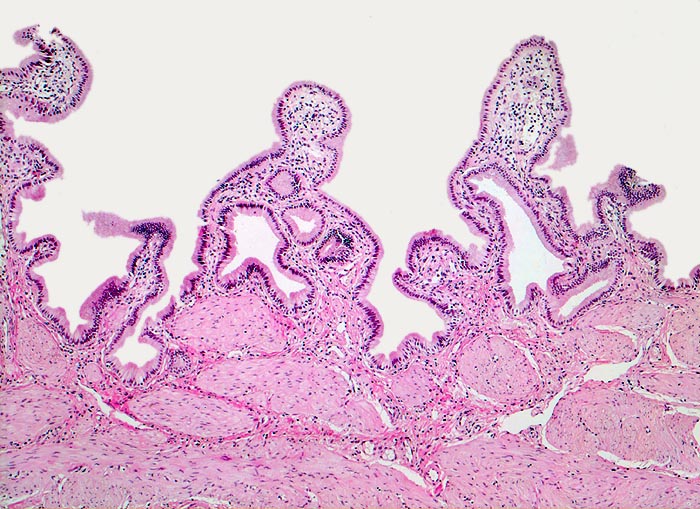

Normale Gallenblase

Gallenblase

Die Gallenblasenschleimhaut bildet unregelmässige Falten, die bedeckt sind von einem hochzylindrischen Epithel. Unterhalb der Mukosa eine dicke Schicht glatter Muskulatur. Anders als in anderen Hohlorganen des Gastrointestinaltrakts fehlen eine Lamina muscularis mucosae und eine Submukosa.

50